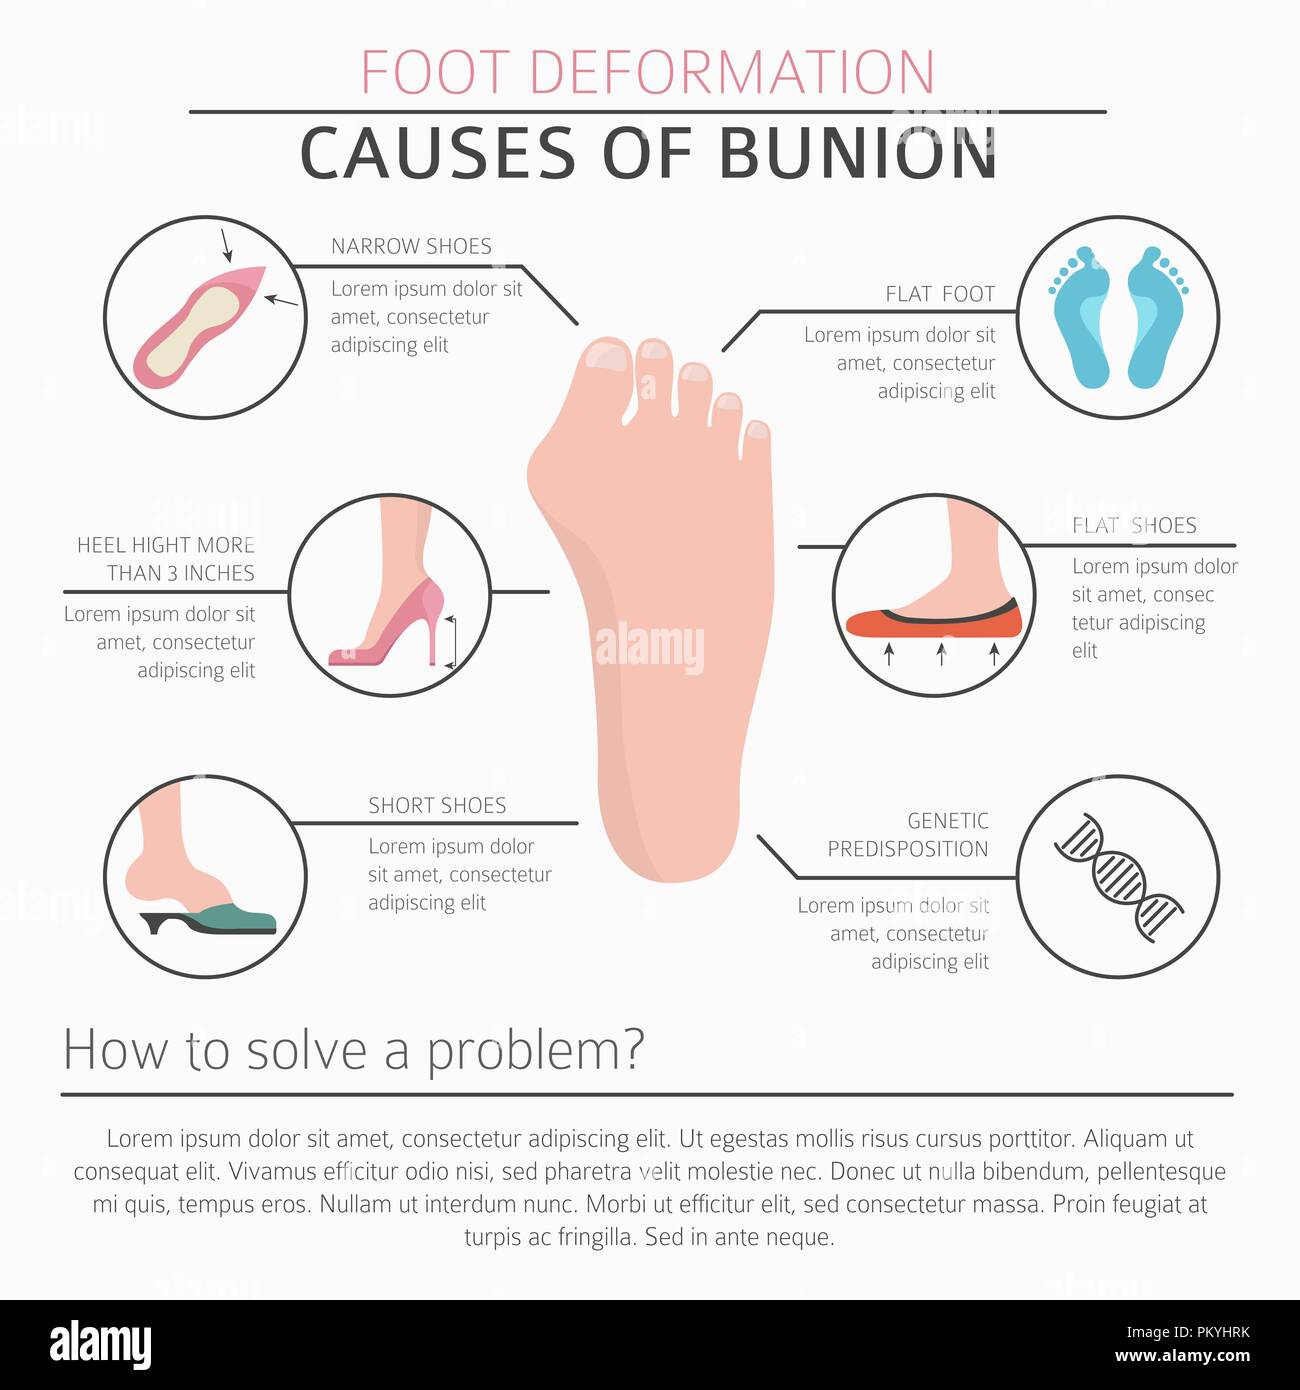

RFPKYHHM–La déformation du pied en tant que maladie médicale infographie. Causes de l'oignon. Vector illustration

RFPKYHRK–La déformation du pied en tant que maladie médicale infographie. Causes de l'oignon. Vector illustration